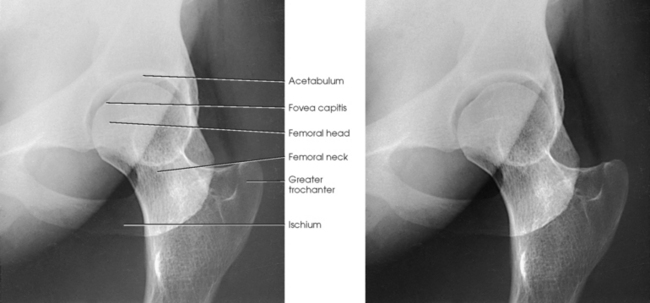

The femur is the longest, strongest, and heaviest bone in the body. The proximal end of the femur consists of a head, a neck, and two large processes: the greater and lesser trochanters (Fig. 7-4). The smooth, rounded head is connected to the femoral body by a pyramid-shaped neck and is received into the acetabular cavity of the hip bone. A small depression at the center of the head, the fovea capitis, attaches to the ligamentum capitis femoris (Fig. 7-5; see Fig. 7-4). The neck is constricted near the head but expands to a broad base at the body of the bone. The neck projects medially, superiorly, and anteriorly from the body. The trochanters are situated at the junction of the body and the base of the neck. The greater trochanter is at the superolateral part of the femoral body, and the lesser trochanter is at the posteromedial part. The prominent ridge extending between the trochanters at the base of the neck on the posterior surface of the body is called the intertrochanteric crest. The less prominent ridge connecting the trochanters anteriorly is called the intertrochanteric line. The femoral neck and the intertrochanteric crest are two common sites of fractures in elderly adults. The superior portion of the greater trochanter projects above the neck and curves slightly posteriorly and medially.

Structures shown: The resulting image shows a lateral projection of the hip including the acetabulum, proximal end of the femur, and relationship of the femoral head to the acetabulum (see Figs. 7-33 and 7-34).